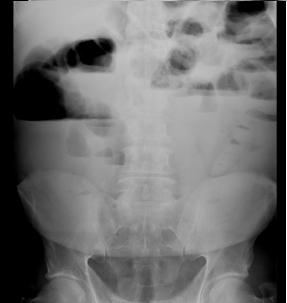

Image des niveaux hydro-aeriques

greliques et coliques d'une occlusion du colon . En

ce cas la valvule de Bauhin est incompetence et

beance. Occlusion par stenose post radique du

tumeur recto-sigmoidienne . |